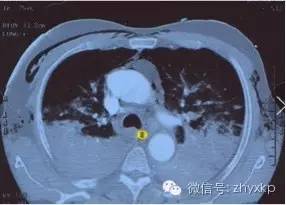

1、呼吸系统疾病:主要是各种严重疾病引起呼吸衰竭时如急性呼吸窘迫综合征、慢性阻塞性肺疾病急性加重、重症哮喘、重症肺炎。